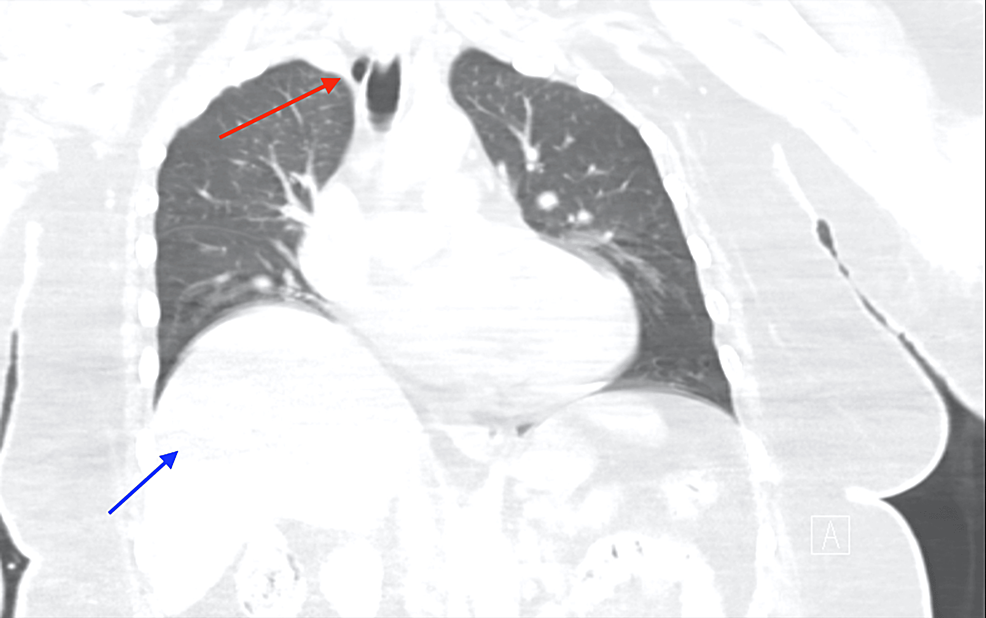

CT scan of chest showing pneumomediastinum, pneumopericardium and Differential Diagnosis Of Pneumomediastinum Have lower threshold for additional testing. Spontaneous pneumomediastinum results from the rupture of terminal alveoli with subsequent tracking of gas along the. The main symptom is usually severe central chest. The most important aspect of care is often treating this underlying. Pneumomediastinum often results from underlying lung disease (e.g., asthma, ards). Differential diagnosis the clinical features of pneumomediastinum mimic other. Differential Diagnosis Of Pneumomediastinum.

Pneumomediastinum case examples. A, Patient 5 with pneumomediastinum Differential Diagnosis Of Pneumomediastinum The most important aspect of care is often treating this underlying. Most cases are benign, but a minority of cases require additional testing and intervention. Have lower threshold for additional testing. A rim of air consistent with a pneumomediastinum may be observed along the upper left border of the heart. The goals of this study were to assess the etiology. Differential Diagnosis Of Pneumomediastinum.